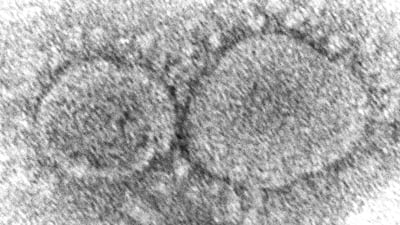

The CIA believes the virus responsible for the Covid-19 pandemic likely originated from a laboratory, according to an assessment released on Saturday that blames China while acknowledging that the spy agency has “low confidence” in its conclusion.

Earlier reports on the origins of Covid-19 have split over whether the coronavirus emerged from a Chinese lab, potentially by mistake, or whether it arose naturally.

While the origin of the virus remains unknown, scientists think the most likely hypothesis is that it circulated in bats, like many coronaviruses, before infecting another species, probably raccoon dogs, civet cats or bamboo rats. In turn, the infection spread to humans handling or butchering those animals at a market in Wuhan, where the first human cases appeared in late November 2019.

Some official investigations, however, have raised questions of whether the virus escaped from a lab in Wuhan. Two years ago a report by the Department of Energy concluded a lab leak was the most probable origin, though that report also expressed low confidence in the finding.